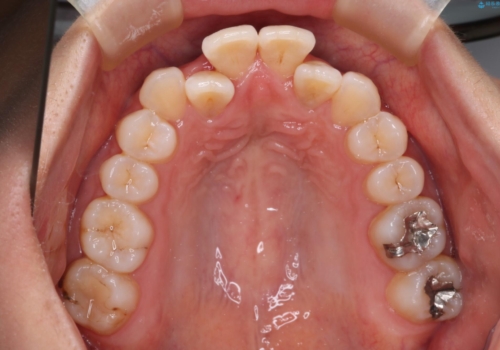

【インビザライン】前歯の凸凹をなおしたい

- 前歯の凸凹を主訴に来院されました。

上顎の急速拡大を行なったのちインビザラインにて治療を行なっております。

今回のケースは後戻りのリスクを低くし、またディスキング量を減らすために上顎の急速拡大を行なっております。